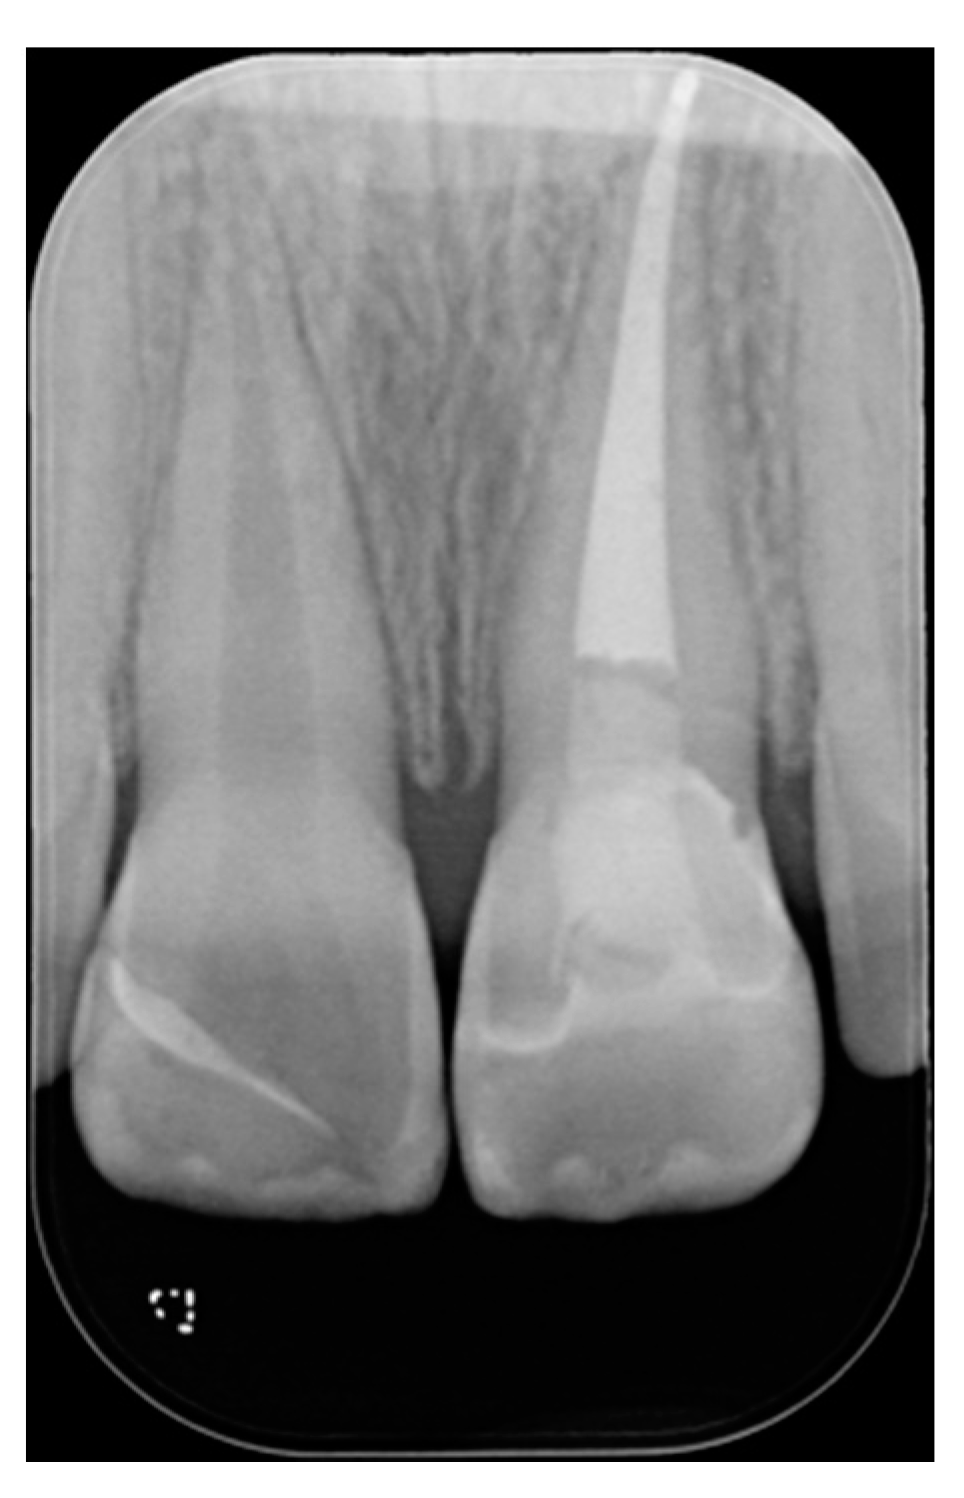

Figure 2.

Initial x-ray. Reprinted from Restauri diretti nei settori anteriori, G. Paolone, S. Scolavino, © 2021, with permission from Quintessence Publishing Italy.

A healthy 10-year boy presented to the dental office after traumatic accident during sport activity. Upper central incisor presented horizontal fracture with no pulp exposure (Figure 1 and Figure 2). Tooth fragment was not retrieved after the traumatic accident. The tooth responded positively to pulp tests (cold and electrical). In order to manage sensitivity and protect the tooth before the restoration appointment, after rubber dam placement, a universal adhesive (Clearfil Universal Bond Quick, Kuraray Noritake Dental, Tokyo, Japan) was applied in self-etch mode followed by a little layer (approximatively 0.5 mm) of flowable composite (Clearfil Majesty ES Flow, A2, Kuraray Noritake Dental, Tokyo, Japan). A silicone impression (Imprint, 3M ESPE, St. Paul, MN, USA) was therefore taken in order to develop a wax-up (Figure 3) and a palatal silicone index (Elite HD+, Zhermack, Badia Polesine, Italy).